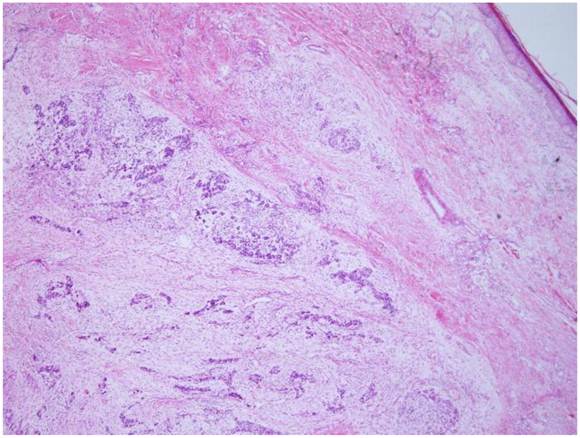

Microscopically, the tumor was well circumscribed without encapsulation and invaded the dermis and subcutis tissues (Figure 1). The tumor was mainly composed of spindle-shaped cells with thin and eosinophilic cytoplasms and atypical nuclei. The tumor cells arranged in bundles and wave pattern in most areas (Figure 2A), and in some areas, arranged radially or in whorls with abundant spoke-like structures (Figure 2B). Myxoid degeneration was visible in some parts of the tumor. Epithelioid differentiation with glandular structures (Figure 2C) appeared in multiple foci, and rosette formation, indicating neuroendocrine differentiation, were also observed (Figure 2D) in these areas. Distinct chondro-differentiation could be seen focally (Figure 3A). In some fields the tumor cells showed eosinophilic cytoplasms with eccentric nuclei, resembling rhabdomyoblasts (Figure 3B), and in the other areas typical lipoblasts were also visible (Figure 3C). Ganglion cells were focally scattered (Figure 3D). Multiple patches of necrosis were observed. Pathological diagnosis was MPNST with heterougenous differentiations, WHO grade IV.

Figure 1

The tumor is located in the dermis without encapsulated (HE X 40).